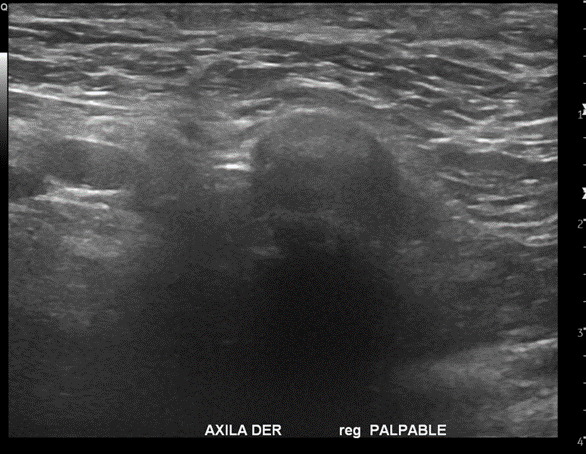

Imagen Ecografía Axilar

Informe Ecografía Axilar:

Hallazgos:

Tejido celular subcutáneo sin alteraciones

No hay imágenes quísticas en el plano evaluado

Estructuras musculares sin alteraciones

No hay líquido libre

Contornos bien definidos

No se identifican adenopatías patológicas

Conclusión:

Sin hallazgos patológicos

Se realiza posteriormente Ecografía Mamaria

En la axila derecha adyacente a cabeza de húmero y en correlación con reg. palpable, se observa área nodular hipoecogénica, ovalada y parcialmente circunscrita, sin señal al Doppler Power, podría corresponder a ganglio axilar inespecífico, se sugiere estudio complementario por antecedente de osteosarcoma escapular operado.

En la región axilar derecha se demuestra una imagen nodular isoecogénica de 16x15mm adyacente a la cabeza humeral como hallazgo.